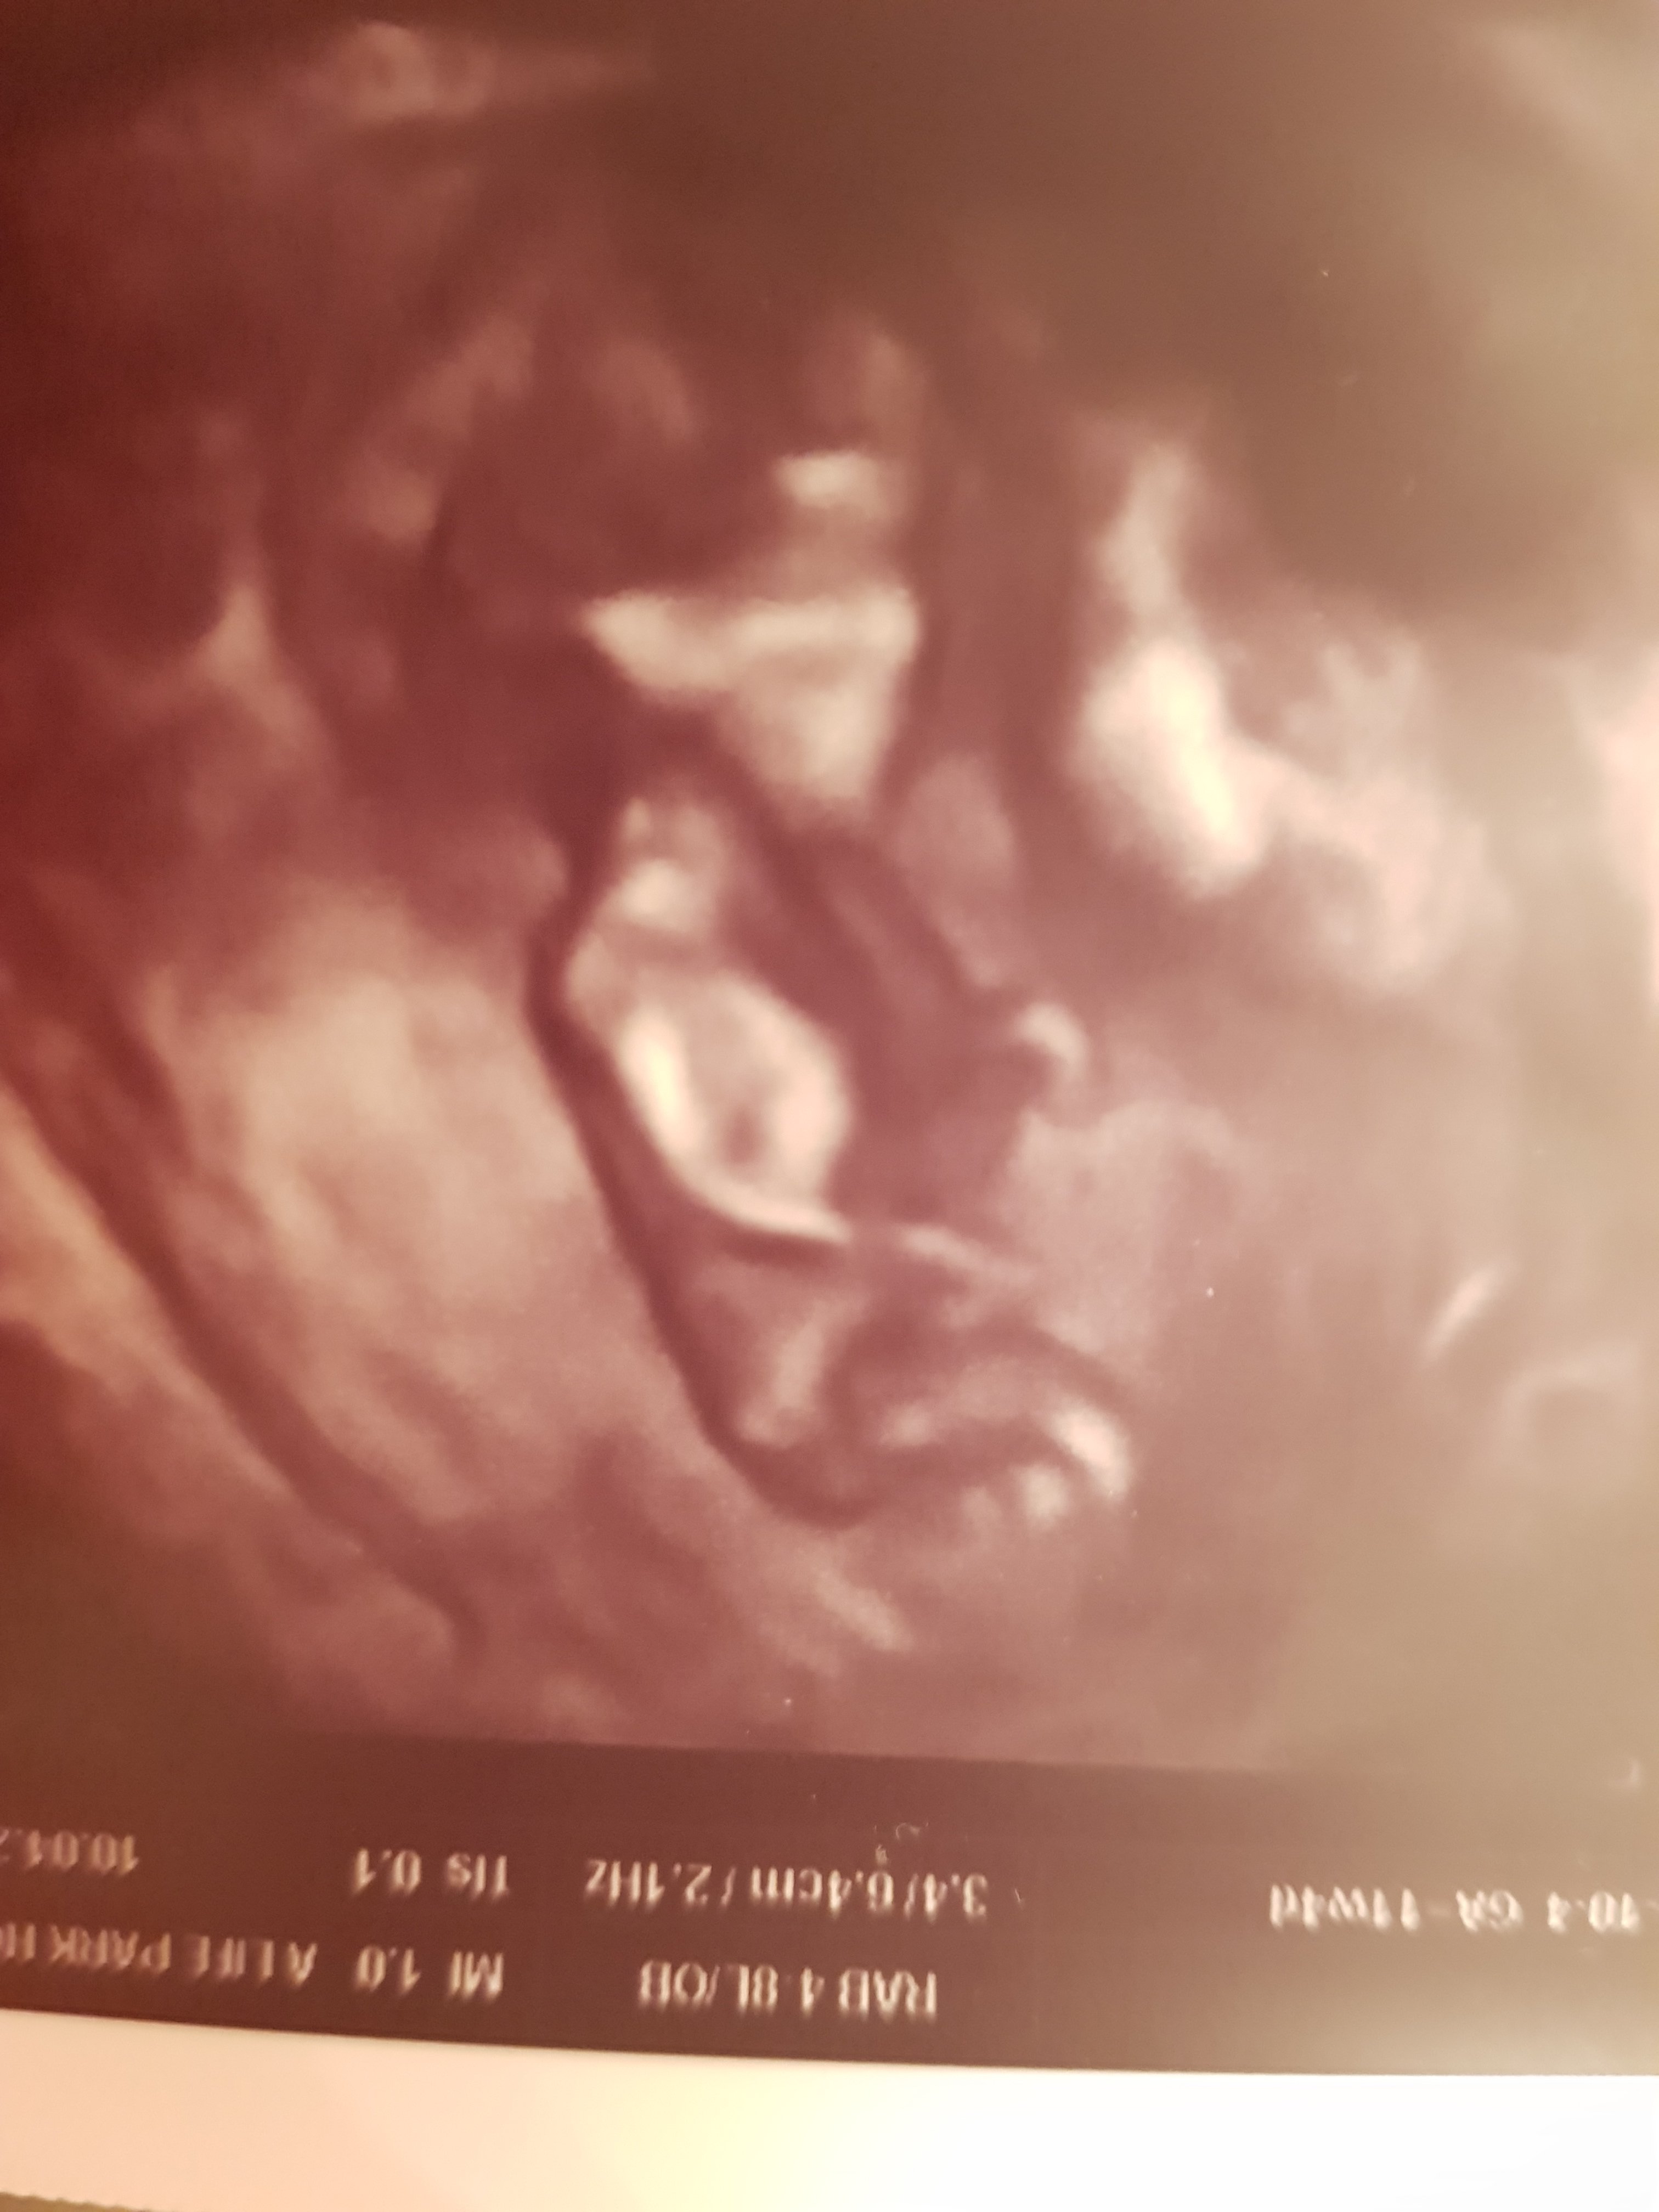

B Boncuk23 Yeni Üye Üye 16 Nisan 2019 #596 Sevimli cadı' Alıntı: Nub çıkıntısı belli olmuyor doktor konumuna göre değerlendirme yapmıştır . Doktor cinsiyetini görebildi mi? Genişletmek için tıkla ... Merhaba rica etsem benim ultrason fotolarıma da bakabilir misiniz teşekkürler Ekli dosyalar 20190411_231719.jpg 859,8 KB · Görüntüleme: 977 20190411_231635.jpg 1.003,5 KB · Görüntüleme: 693 20190411_231645.jpg 1 MB · Görüntüleme: 755 20190411_231635.jpg 1.003,5 KB · Görüntüleme: 768

Sevimli cadı' Alıntı: Nub çıkıntısı belli olmuyor doktor konumuna göre değerlendirme yapmıştır . Doktor cinsiyetini görebildi mi? Genişletmek için tıkla ... Merhaba rica etsem benim ultrason fotolarıma da bakabilir misiniz teşekkürler